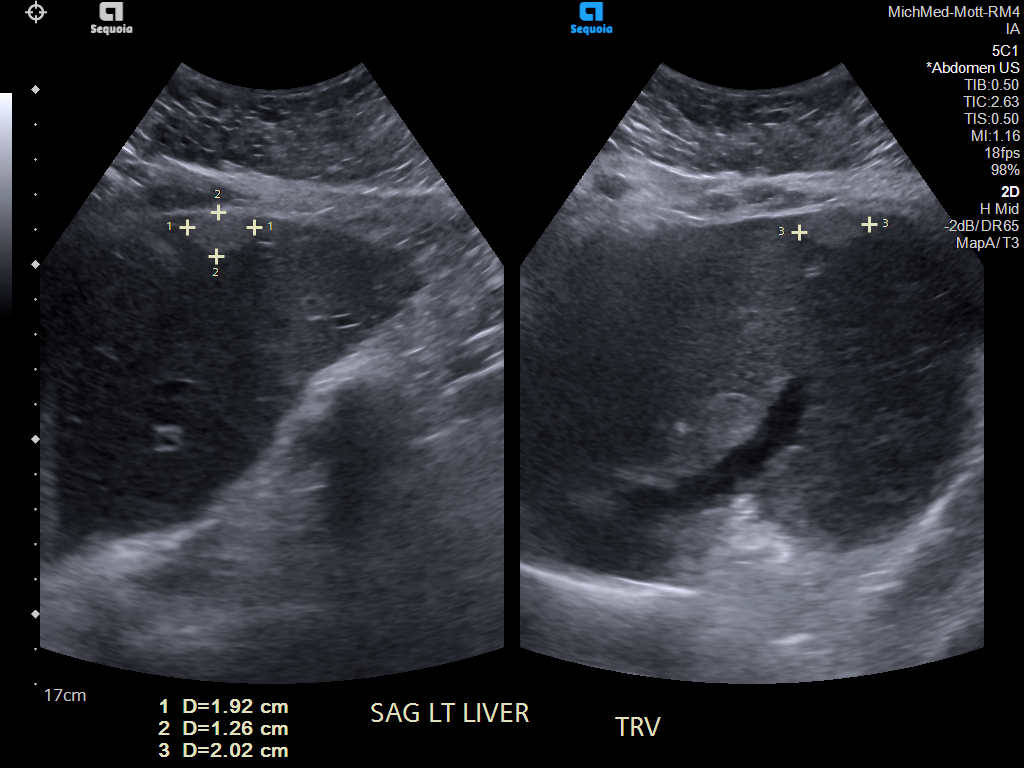

69 M with PMH of HCV cirrhosis & HCC s/p resection in 14 years ago presenting today for a screening ultrasound.

135/73 mmHg / 78 bpm / 16 breaths/min / 96.4°F

sclerae anicteric, no jaundice

CMP wnl, AFP 5